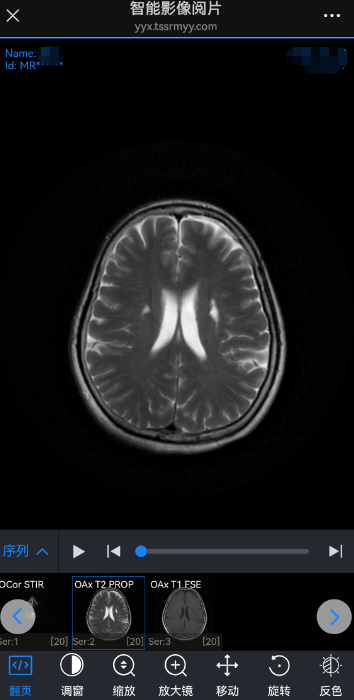

STEP1 扫描纸质报告单右上角二维码 STEP2 扫描登记小票上方二维码 STEP3 为了保护患者隐私,保证信息安全。 扫描二维码之后需要输入手机号后4位或者身份证号码后6位进行身份验证。验证成功之后才能看到本次检查结果的原始报告和影像文件。 STEP4 点击“报告单”,可查看本次检查的原始报告单。 STEP5 点击“查看影像”,可查看本次检查的原始影像(DICOM格式)。该影像可实现放大、缩小、旋转等功能。